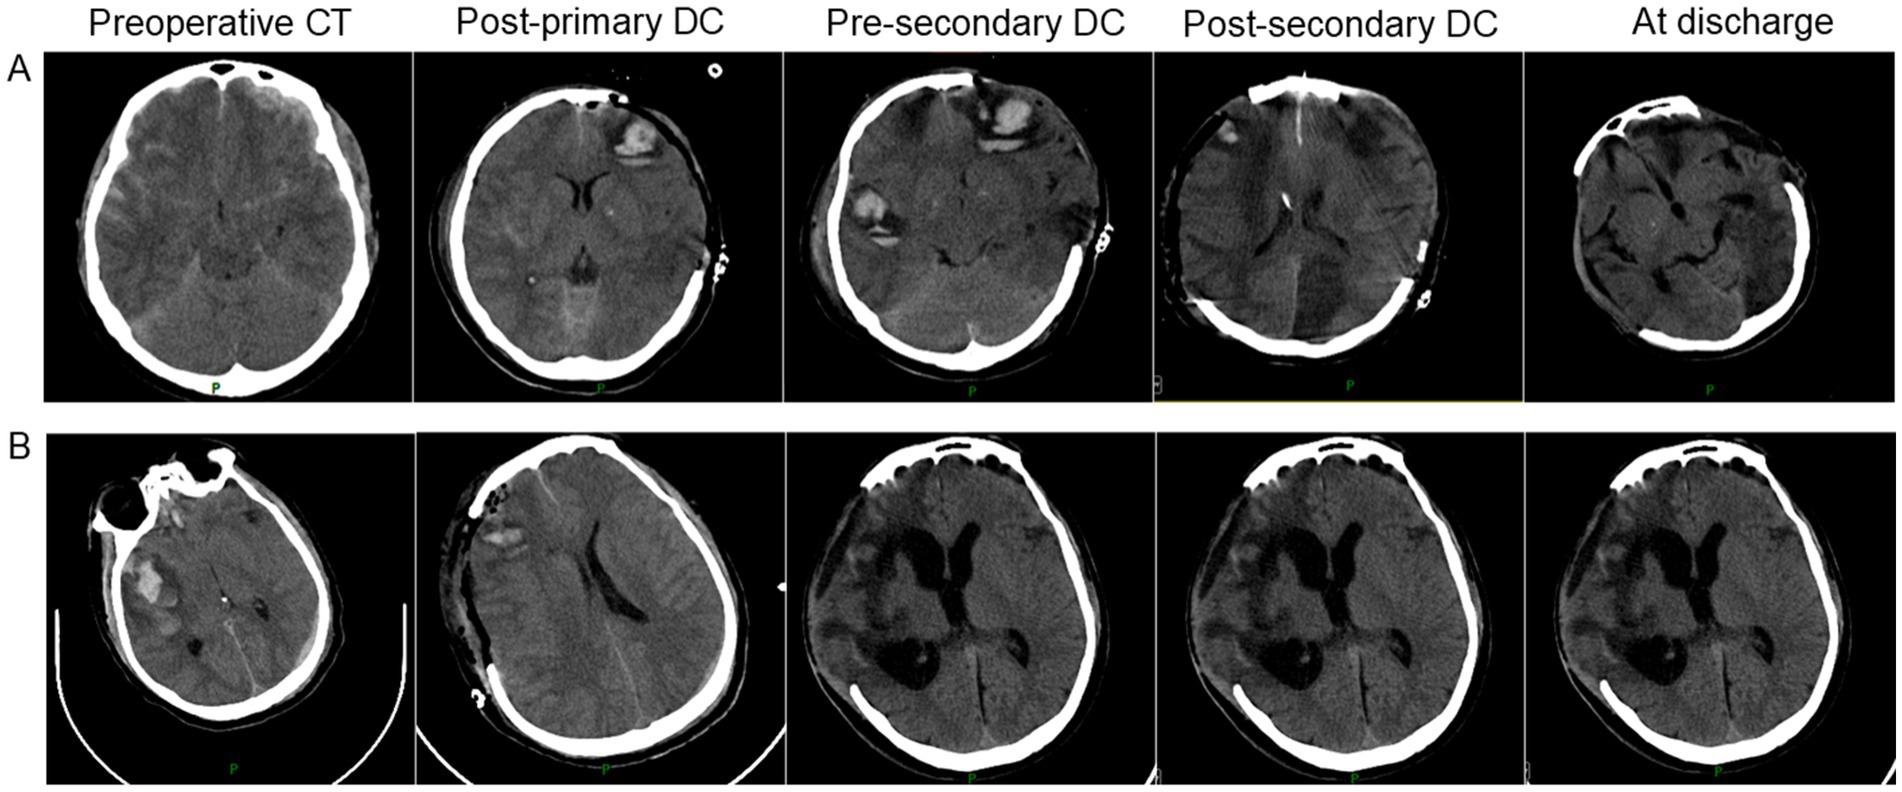

In summary, to further illustrate our findings, we have selected two representative cases for presentation, as shown in Figure 2.

Figure 2

CT scan images show a series of five brain scans over time for two patients, labeled A and B. Each row progresses from preoperative CT, post-primary decompressive craniectomy (DC), pre-extended DC, post-extended DC, to at discharge. The images illustrate changes in brain structure and swelling reduction after surgeries.

Figure 2. Representative cases of secondary decompressive craniectomy in severe traumatic brain injury. (A) An adult patient underwent right-sided primary DC (9 × 9 cm) for bilateral frontal contusions and left occipital epidural hematoma. Due to progressive cerebral edema and ICP elevation (40 mmHg), an ipsilateral secondary DC (12 × 15 cm) was performed. GOSE at 6 months was 3; complications included pneumonia, post-traumatic epilepsy, and hydrocephalus. (B) An adult patient underwent left-sided primary DC (10 × 11 cm) for a large subdural hematoma. Persistent elevated ICP (34 mmHg) and new hematoma formation led to a contralateral (right-sided) secondary DC (12 × 15 cm). GOSE at 6 months was 4; complications included pneumonia and deep vein thrombosis.